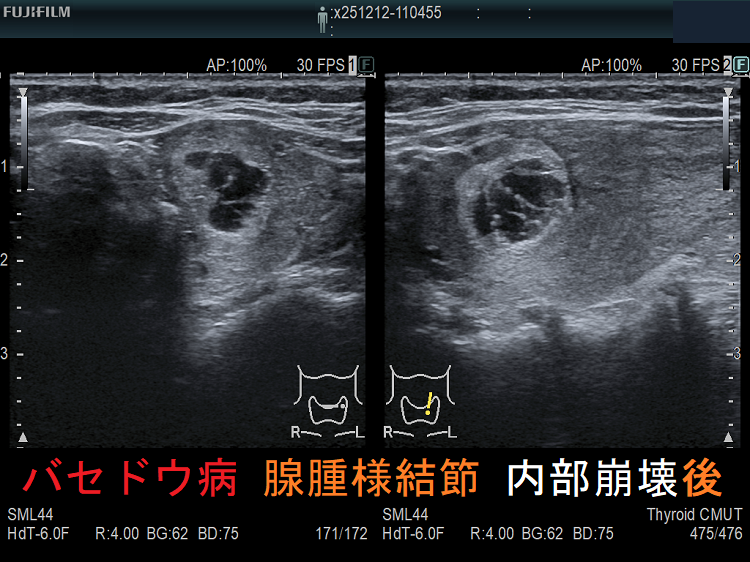

穿刺細胞診後内部融解

ケース①